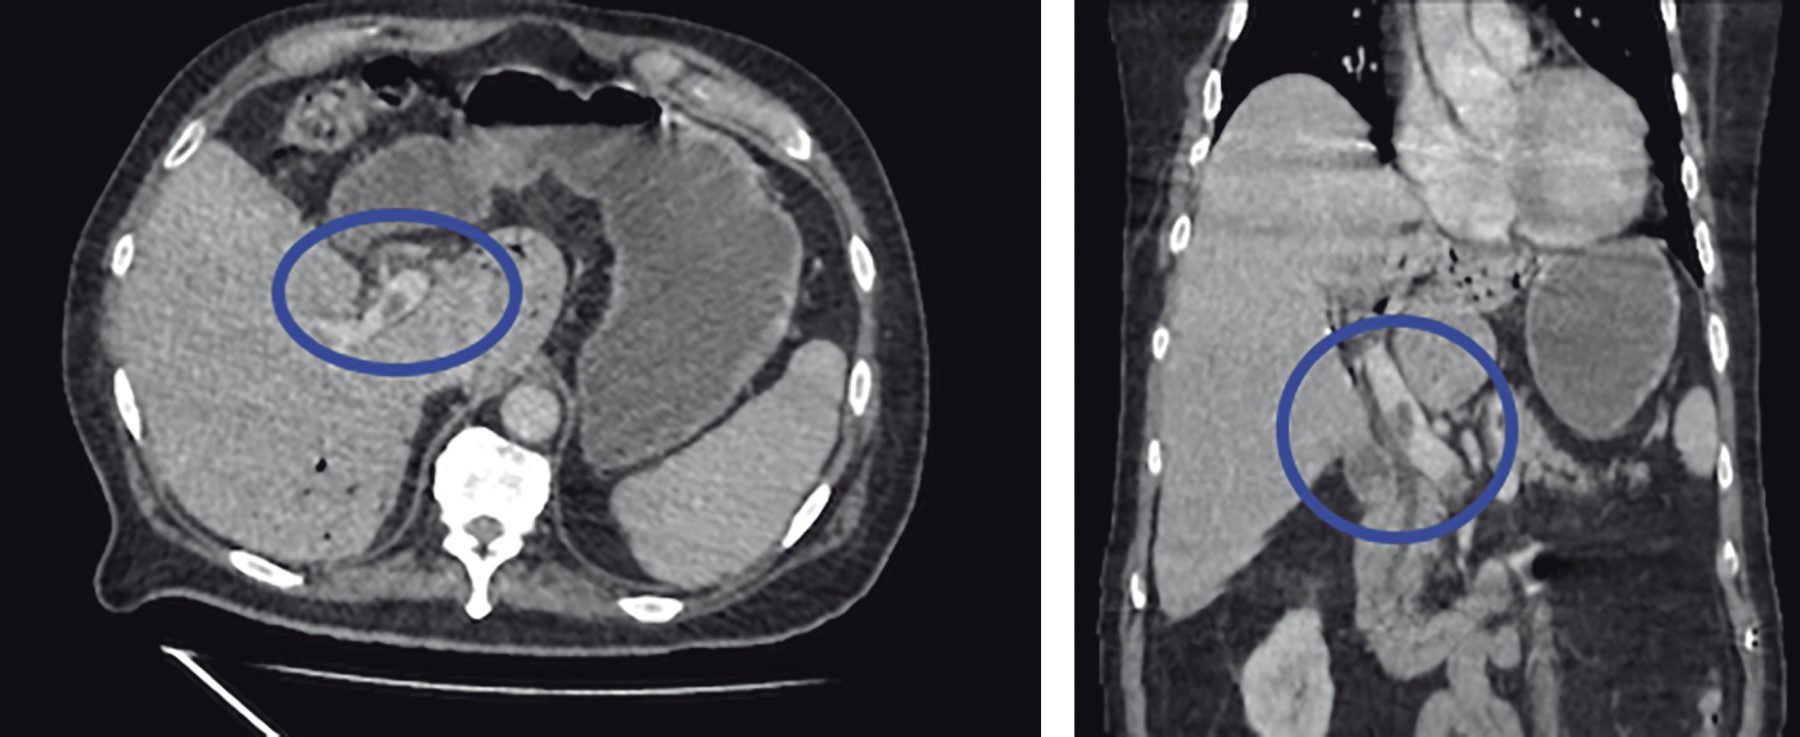

We present the case of a 77-year-old male with a history of diabetes mellitus 2 and long-standing systemic arterial hypertension, surgical history of laparoscopic cholecystectomy six years ago, and cardiac catheterization for chronic ischemic heart disease. His current condition began 10 days before his admission with diffuse abdominal pain in the lower quadrants, as well as an attack on his general condition accompanied by asthenia and hyporexia. An external physician with antibiotic therapy managed him. On arrival at the Emergency Department, he presented tachycardia and a tendency to hypotension accompanied by altered alertness. Physical examination revealed an inflammatory plastron in the left lower quadrant that aroused pain during manipulation; however, there was no evidence of peritoneal irritation. Laboratory tests showed leukocytes 13,400 mm3, neutrophilia 92.9%, and lactate 3.9 mmol/l. A contrast abdominopelvic CT scan was requested, showing portal vein thrombosis (Figure 1), portal pneumatosis (Figure 2), and diverticular disease (Figure 3). Due to the above findings, initial management with intravenous solutions and empirical broad-spectrum antibiotic therapy with piperacillin-tazobactam 4.5 g IV every 8 hours was started; after stabilizing management, exploratory laparotomy was performed, where sigmoidectomy and terminal colostomy were performed due to the findings of diverticular perforation (Figures 4 and 5) and purulent inflammatory plastron in the mesosigmoid with special distribution in the path of the inferior mesenteric vein. Samples for cultures were taken. Postoperative management was performed in the intensive care unit, and antibiotic therapy was directed to E. coli. Total parenteral nutrition and anticoagulant therapy were started with 60 mg of enoxaparin subcutaneously (SC) every 12 hours. The patient had a favorable clinical evolution thanks to the multidisciplinary management provided. He was discharged one week after the surgical procedure without any complications. He was referred to the outpatient clinic one week after his discharge. He was tolerating the oral route with a functional stoma and with the wound intact. The histopathology report revealed a complicated diverticular disease.

Figure 3

Figure 4

Figure 5